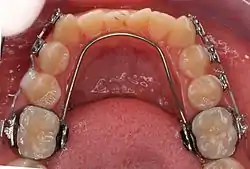

A lingual arch is an orthodontic device which connects two molars in the upper or lower dental arch. The lower lingual arch (LLA) has an archwire adapted to the lingual side of the lower teeth. In the upper arch the archwire is usually connecting the two molars passing through the palatal vault, and is commonly referred as "Transpalatal Arch" (TPA). The TPA was originally described by Robert Goshgarian in 1972. TPAs could possibly be used for maintaining transverse arch widths, anchorage in extraction case, prevent buccal tipping of molars during Burstonian segmented arch mechanics, transverse anchorage and space maintenance.

LLA and TPA are fabricated by placing bands on the molars. These are connected to the archwire. The wire can be soldered to the bands or inserted into lingual sheaths welded to the molar band (removable LLA and TPA).

Transpalatal arch